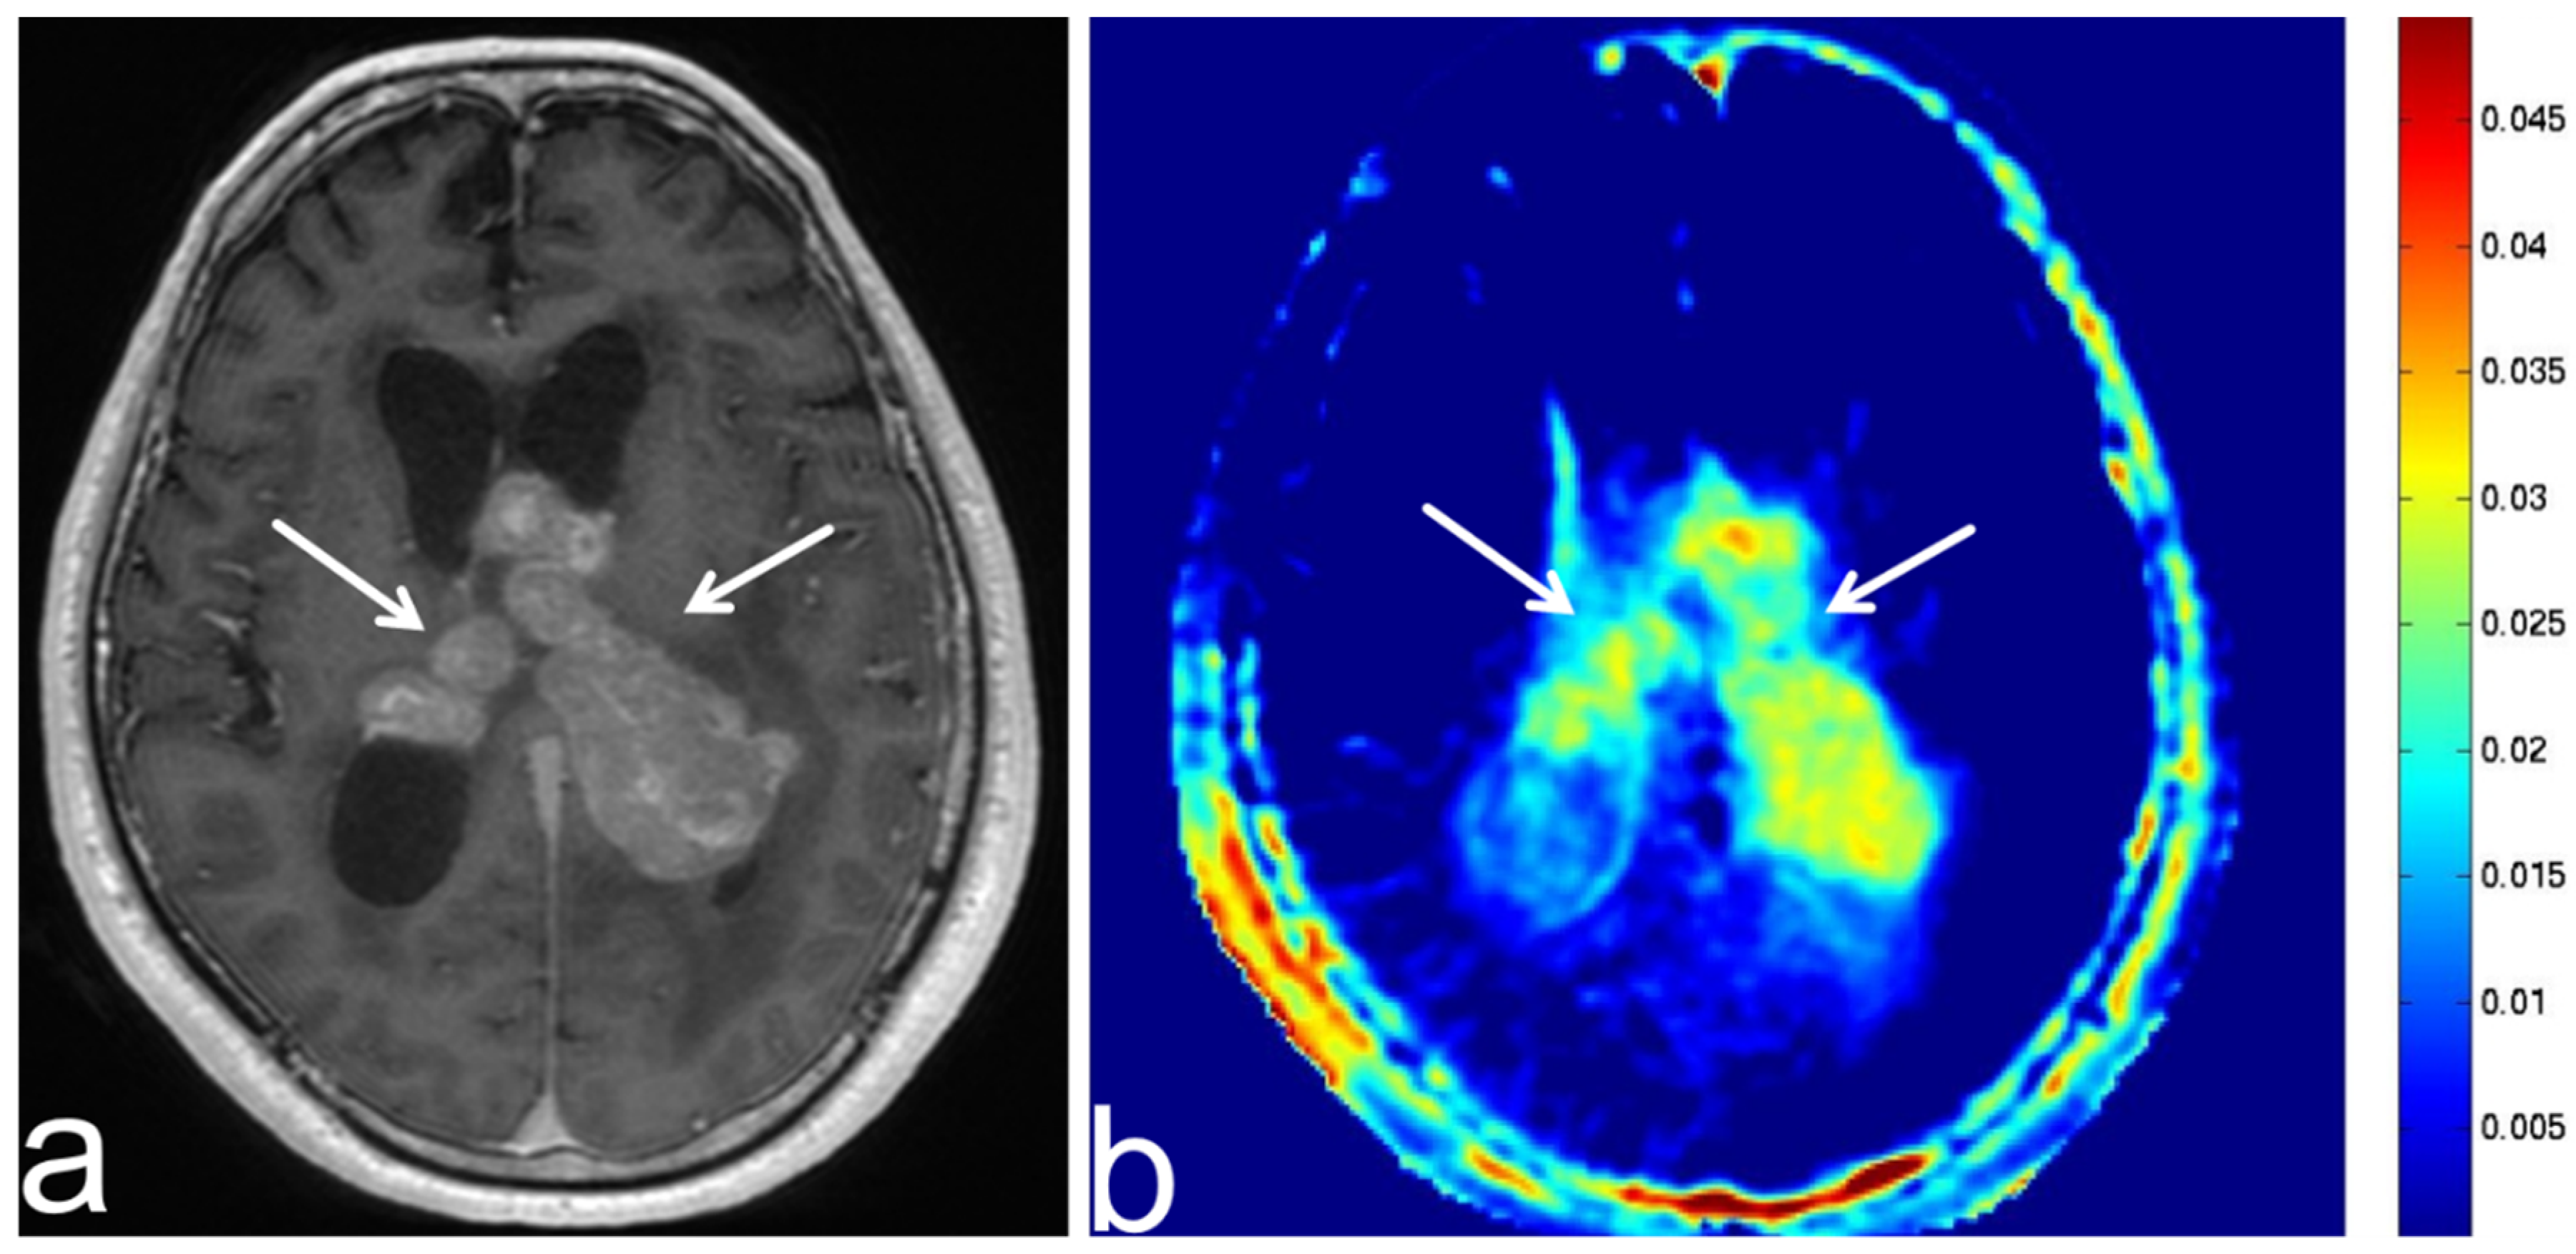

8.4. Progressive Multifocal Leukoencephalopathy